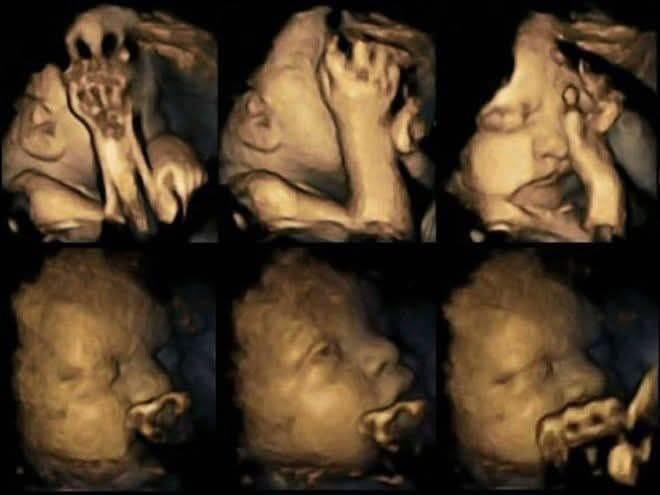

Thai nhi phản ứng với khói thuốc ngay từ trong bụng mẹ

Theo kết quả ghi nhận được của các chuyên gia thuộc Đại học Durham, rõ ràng là thai nhi có những biểu hiện rất khác thường khi bà bầu hút thuốc lá hoặc khi thai phụ tiếp xúc với khói thuốc, cụ thể là em bé thường xuyên đưa tay lên che mặt và khuôn mặt thì rất căng thẳng và nhăn nhó. Kết quả nghiên cứu thông qua việc siêu âm thai cũng cho hay, phụ nữ tiếp xúc với khói thuốc lá trong thai kỳ có thể ảnh hưởng đến hệ thống thần kinh trung ương, và làm trì hoãn sự phát triển của bộ phận này.